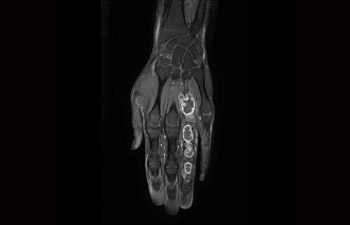

Hand/Wrist with tumor